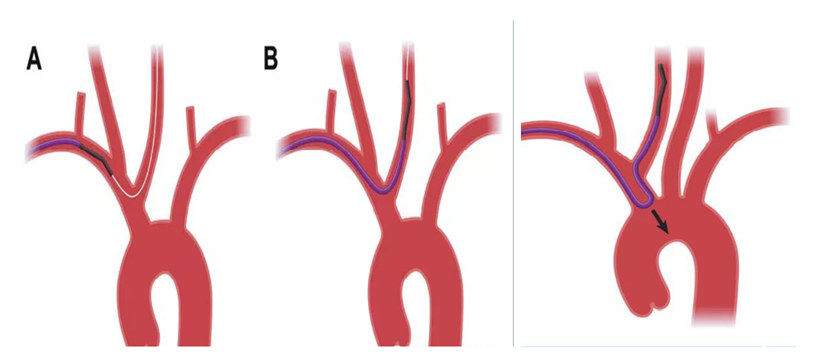

经绕动脉完成的颈内动脉介入通路:

选择4F125猪尾或5F125西蒙或125单弯西蒙形状带6F导引导管较好,没有125导管的情况下,6F导引导管不接Y阀内衬100cm造影导管到位后撤出造影导管,再连接Y阀。可以完成通路建立。

缺点6F导引导管仅能通过7-8mm以下自膨支架,8mm以上的通过困难。

1、经绕动脉完成的左侧颈内动脉介入通路建立示意图

桡动脉入路治疗CAS--左侧颈动脉(西蒙导管导引)

关键技术:无交换 导引导管到位技术(外管+西蒙导管)